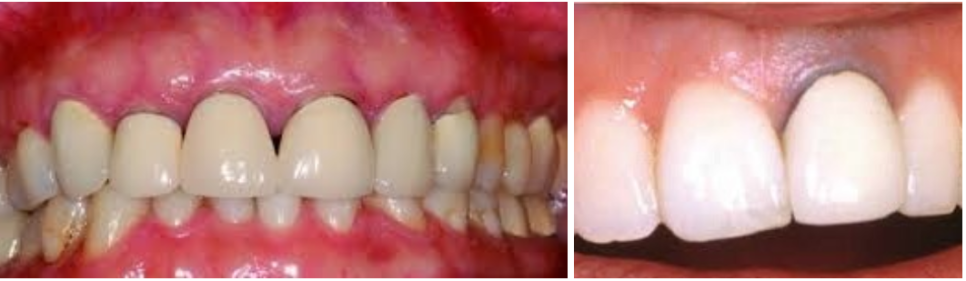

pfm으로 보철물을 제작시 시간이 지나면 사진처럼 검게 보입니다, 앞니에는 적합하지 않는 재료입니다

Pfm은 안에금속이들어가고바깥은치아색도자기로만들어지는데 푸른빛이 비춰보여

앞니에는사용하지않고주로어금니임플란트에사용합니다.

65세이상어르신들에게적용되는보험임플란트는pfm 보철만 인정이됩니다.